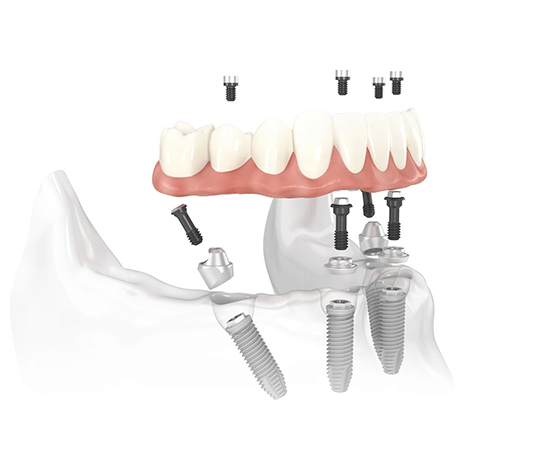

Il sistema Fast&Fixed è un'alternativa immediata. Questa procedura ti permetterà di ritrovare il tuo sorriso in un unico intervento. Il risultato è immediato e recupererai autostima e fiducia in te stesso.